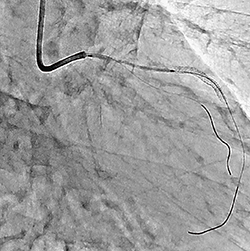

2.EP/SHDサポートアプリケーション“マルチモダリティロードマップ”

Rite Editionでは,Cアームの回転撮影により得られた3D-angio画像とともに,術前に撮影したCTやMRIなどの3Dボリュームデータをロードマップとして,リアルタイムに透視像に重ね合わせ,手技のナビゲーションとして活用可能である(図5)。透視像と重ね合わされた3D画像は,手技中に考えられる装置の機械的動作(Cアーム回転,寝台移動,画像の視野拡大など)に追随して表示されるため,一度位置合わせを行えば,マップ画像を撮影する時間や手間に加え,被ばくや造影剤が削減でき,マルチモダリティ画像を有効に活用した,より低侵襲なIVRが可能となる。

図5 EP/SHDサポートアプリケーション:

マルチモダリティロードマップ